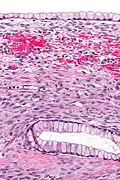

Micrograph showing a mucinous cystadenoma of the ovary. H&E stain.

Mucinous cystadenoma is a benign cystic tumor lined by a mucinous epithelium. It is a type of cystic adenoma (cystadenoma).